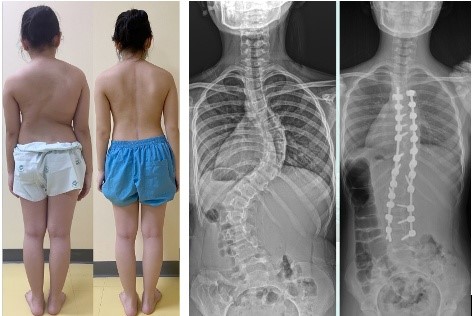

ภาพแสดงเปรียบเทียบลักษณะภายนอกและภาพรังสีวินิจฉัยก่อนและหลังเข้ารับการรักษาผ่าตัดภาวะกระดูกสันหลังคดเอียง